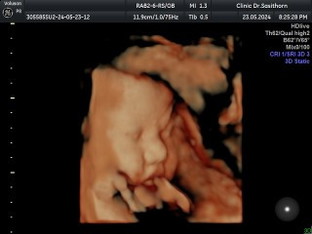

ป้าๆน้าๆช่วยให้กำลังใจหรือปรอบใจแม่หนูหน่อยน๊า อยากคลอดเองแต่น้องหนัก4189g หมอนัดผ่า26 พ.ค นี้แล้วงับ แอบกลัว🥲🥲🥲